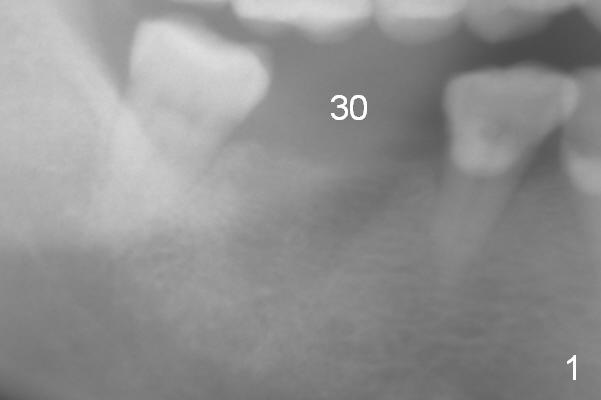

Osteotomy in Healed Site

A 52-year-old lady has lost #30 for several years, but the socket outline persists with low bone density (Fig.1 (trimmed from panoramus),2). Osteotomy should be underprep. Bone height allows to placement of a 14 mm implant (Fig.3). Still initial depth will be 12 mm.